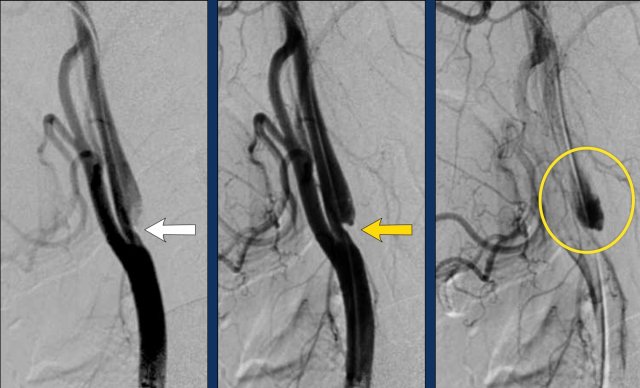

Pseudo-occlusion with DSA

The DSA gives us comparable images.

In this patient during catheter angiography, first there was a typical waterpaint appearance of the contrast in the ICA, which simulated a proximal occlusion in the ICA.

However the catheter could easily be advanced into

the distal ICA.

After a more

forceful contrast injection there is a typical carotid-top occlusion on the

lateral view (just above the level of the ophthalmic artery.

There is no contrast filling

of the intracerebral vessels.